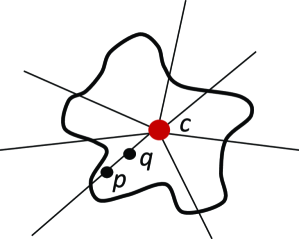

where is the mask of an ellipse parametrized by . As minimizing such a term is not straightforward, the authors optimize the energy functional iteratively, i.e. by finding the best for a fixed and then optimizing for a fixed . For complex shapes that are hard to parametrize, an alternative approach is to fit a shape template to the current segmentation as proposed in (Freedman and Zhang, 2005). Veksler (2008) proposed to incorporate a more general class of shapes, known as star shapes, into graph-based segmentation. In Veksler’s work, it is assumed that the center point () of the object is given. According to their definition, “an object has a star shape if for any point inside the object, all points on the straight line between the center and also lie inside the object” (Figure 13). The following pairwise term was introduced to impose the star shape prior:

| (33) |

This prior is particularly useful for segmentation of convex objects, e.g. optic cum and disc segmentation (Bai et al., 2014).